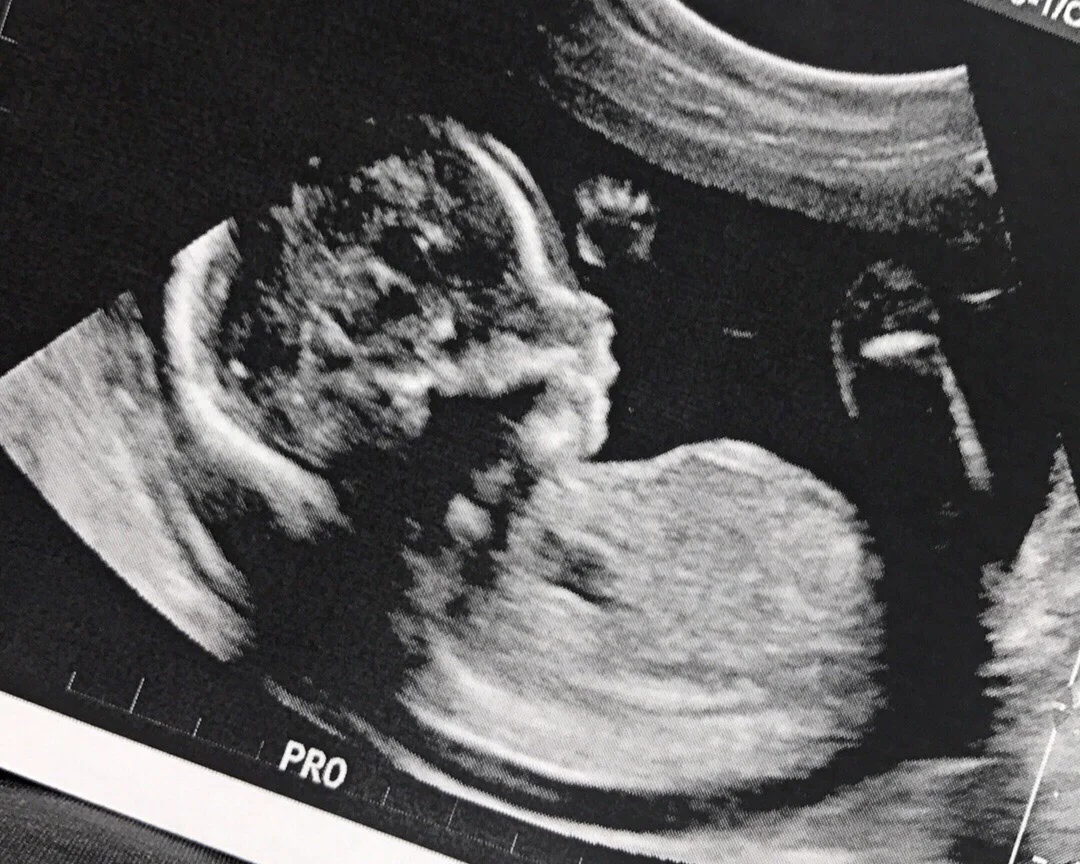

We love you little baby C, we can't wait to meet you in June.

P.S. That's little baby C's little foot!